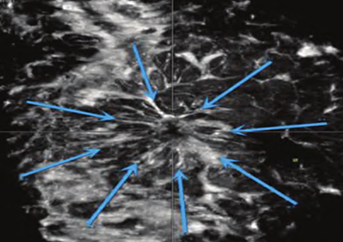

汇聚征

低回声肿块周边呈现向中心汇聚的放射状排列高回声